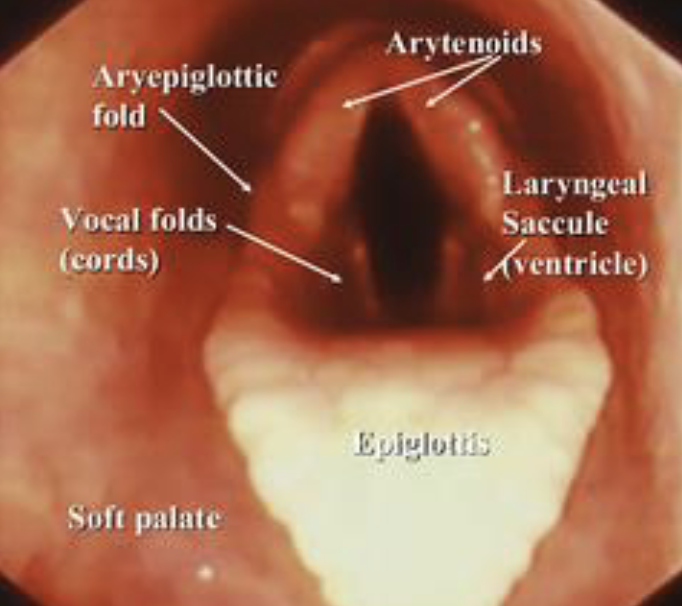

larynx endoscopic view

arytenoids, aryepiglottic fold, vocal folds, laryngeal saccule, epiglottis

laryngeal hemiplagia

half paralysis

aBduct- to move away from midline done by dorsal cricoarytenoid muscle (innervated by left recurrent laryneal nerve)

aDduct- move towards middline